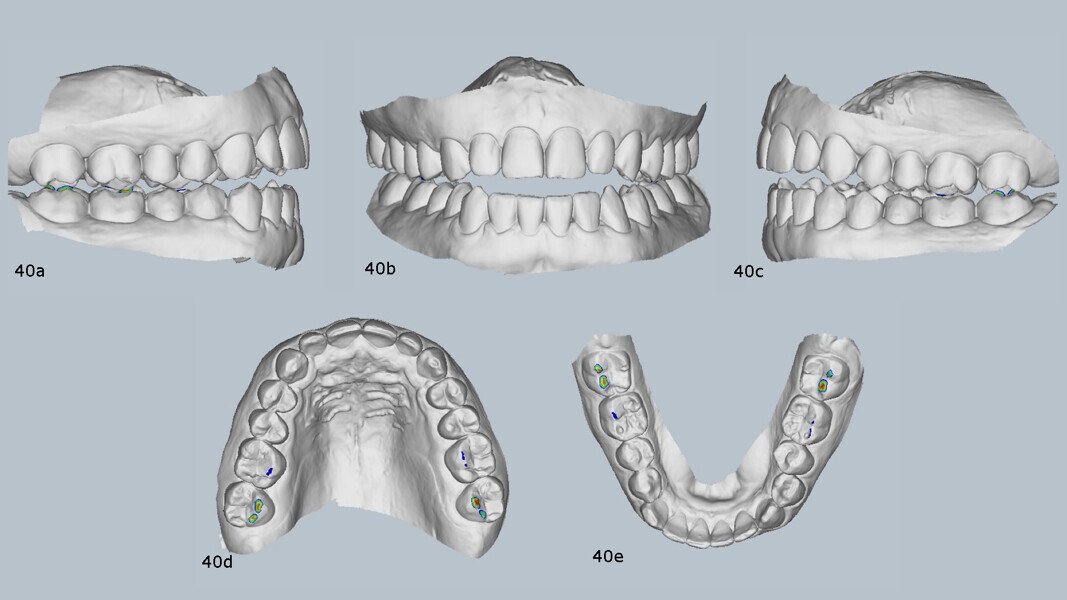

TMJ analysis

The patient reported joint and orofacial muscle pain, headaches, neck pain and nocturnal bruxism. CBCT imaging showed small condyles with flattened articular surfaces. The right condyle was slightly posteriorly positioned within the mandibular fossa (Fig. 39). Additionally, a virtual articulator mounting using the MODJAW system revealed that there was a significant discrepancy between maximum intercuspation and centric occlusion and that the first occlusal contact was at tooth #27 (Fig. 40).